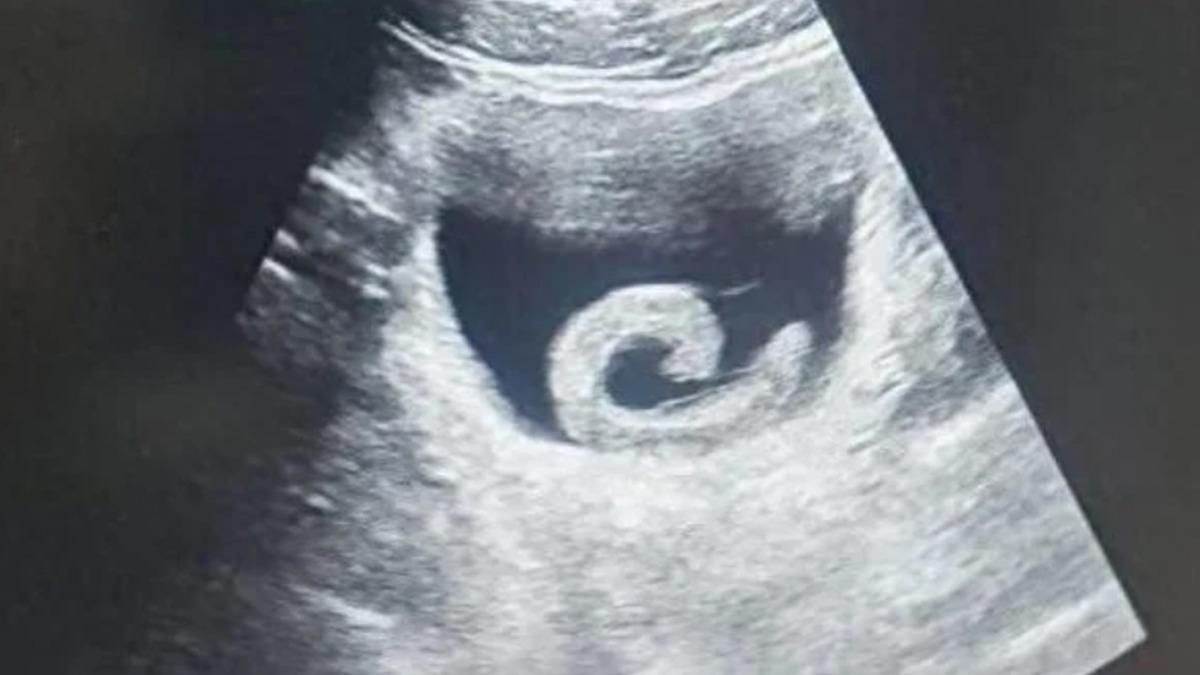

Sülük, Zheng'e o kadar dayanılmaz bir acı vermişti ki, yerel bir hastanenin acil servisine başvurmaktan başka çaresi kalmamıştı. Vaka karşısında doktorlar bile anlattıklarını duyunca şok oldular. Ultrason muayenesi, gerçekten de mesanesinde bir sülük olduğunu doğruladı ve doktorlar paraziti çıkarmak ve gencin hayatını kurtarmak için acil bir ameliyata hazırlandılar.